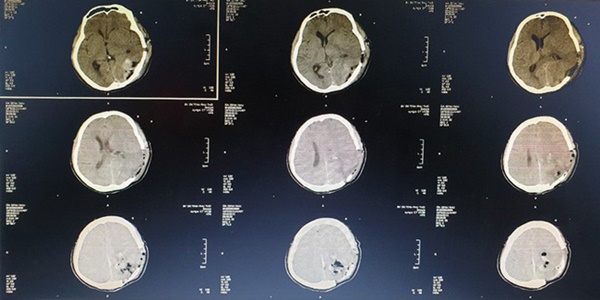

Phim chụp cho trường hợp bệnh nhân N.

Tại bệnh viện Đa khoa tỉnh Phú Thọ, người bệnh được chỉ định chụp CT sọ não, kết quả cho thấy ổ sán não khổng lồ ở bán cầu trái và vùng thái dương đỉnh phải. Phù não đè đẩy đường giữa. Bệnh nhân được chỉ định can thiệp ngoại khoa cấp cứu vào lúc 23 giờ ngày 09/03.